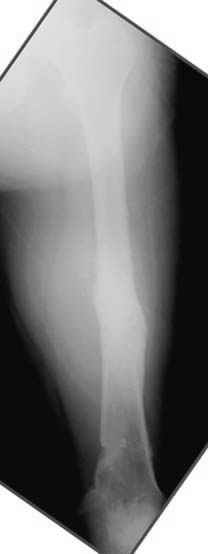

Отправитель: Djoldas Kuldjanov 23 Ноябрь 2004, 18:21

пластическая модель; и коррекция бедра аппаратом Илизарова.

Имею другие снимки тоже, получится как отчет о моей работе.

Отправитель: Evgueny Tschekashkin 24 Ноябрь 2004, 21:09

хотя даже если бы и инфекция , то nail exchange с рассверливанием канала - вариант дебрайдмента) Я думаю, что последовательность развития событий:

Узкий к-м канал - тонкий гвоздь- усталостный перелом дистальных винтов - развитие нестабильности и как ее результат остеолиз вокруг гвоздя - деформация анатомической оси бедра. Похоже, что я понял почему аппарат, а не новый гвоздь:-)

• Re: Hip joint

Отправитель: Alexander Chelnokov 24 Ноябрь 2004, 21:11

ET> хотя даже если бы и инфекция , то nail exchange с рассверливанием канала -

ET> вариант дебрайдмента)

Да, но если, скажем, течет из инфицированных каналов запирающих винтов, да инфекция в дистальном метафизе бедра - устанешь сверлить.

Аппарат в таком случае средство из серии "тише едешь - дальше будешь".

ET> Я думаю, что последовательность развития событий:

[...]

ET> деформация анатомической оси бедра.

Да, наверно. Но если ничего другого нету, ту небольшую деформацию можно было устранить дистрактором одномоментно ввести другой гвоздь.

Отправитель: Evgueny Tschekashkin 24 Ноябрь 2004, 21:13

> Да, но если, скажем, течет из инфицированных каналов запирающих винтов, да инфекция в дистальном метафизе бедра - устанешь сверлить.

ЕТ-Теоретически это возможно, а практически трудно представить - все-таки уровень медицинского сервиса высок, поэтому вряд ли инфекционное воспаление может зайти так далеко.....

ET> Похоже, что я понял почему аппарат, а не новый гвоздь:-)

> Тогда делись догадкой скорей!

ЕТ - Изначально костно-мозговой канал бедра был узкий, дальнейшее его рассверливание ещё больше скомпрометирует прочность бедра( латеральный кортекс дистального отломка уже истончен), приведет к дефекту наружной стенки - хотя это только мои догадки - хотелось бы знать мнение Джолдаса о выбранной тактике.